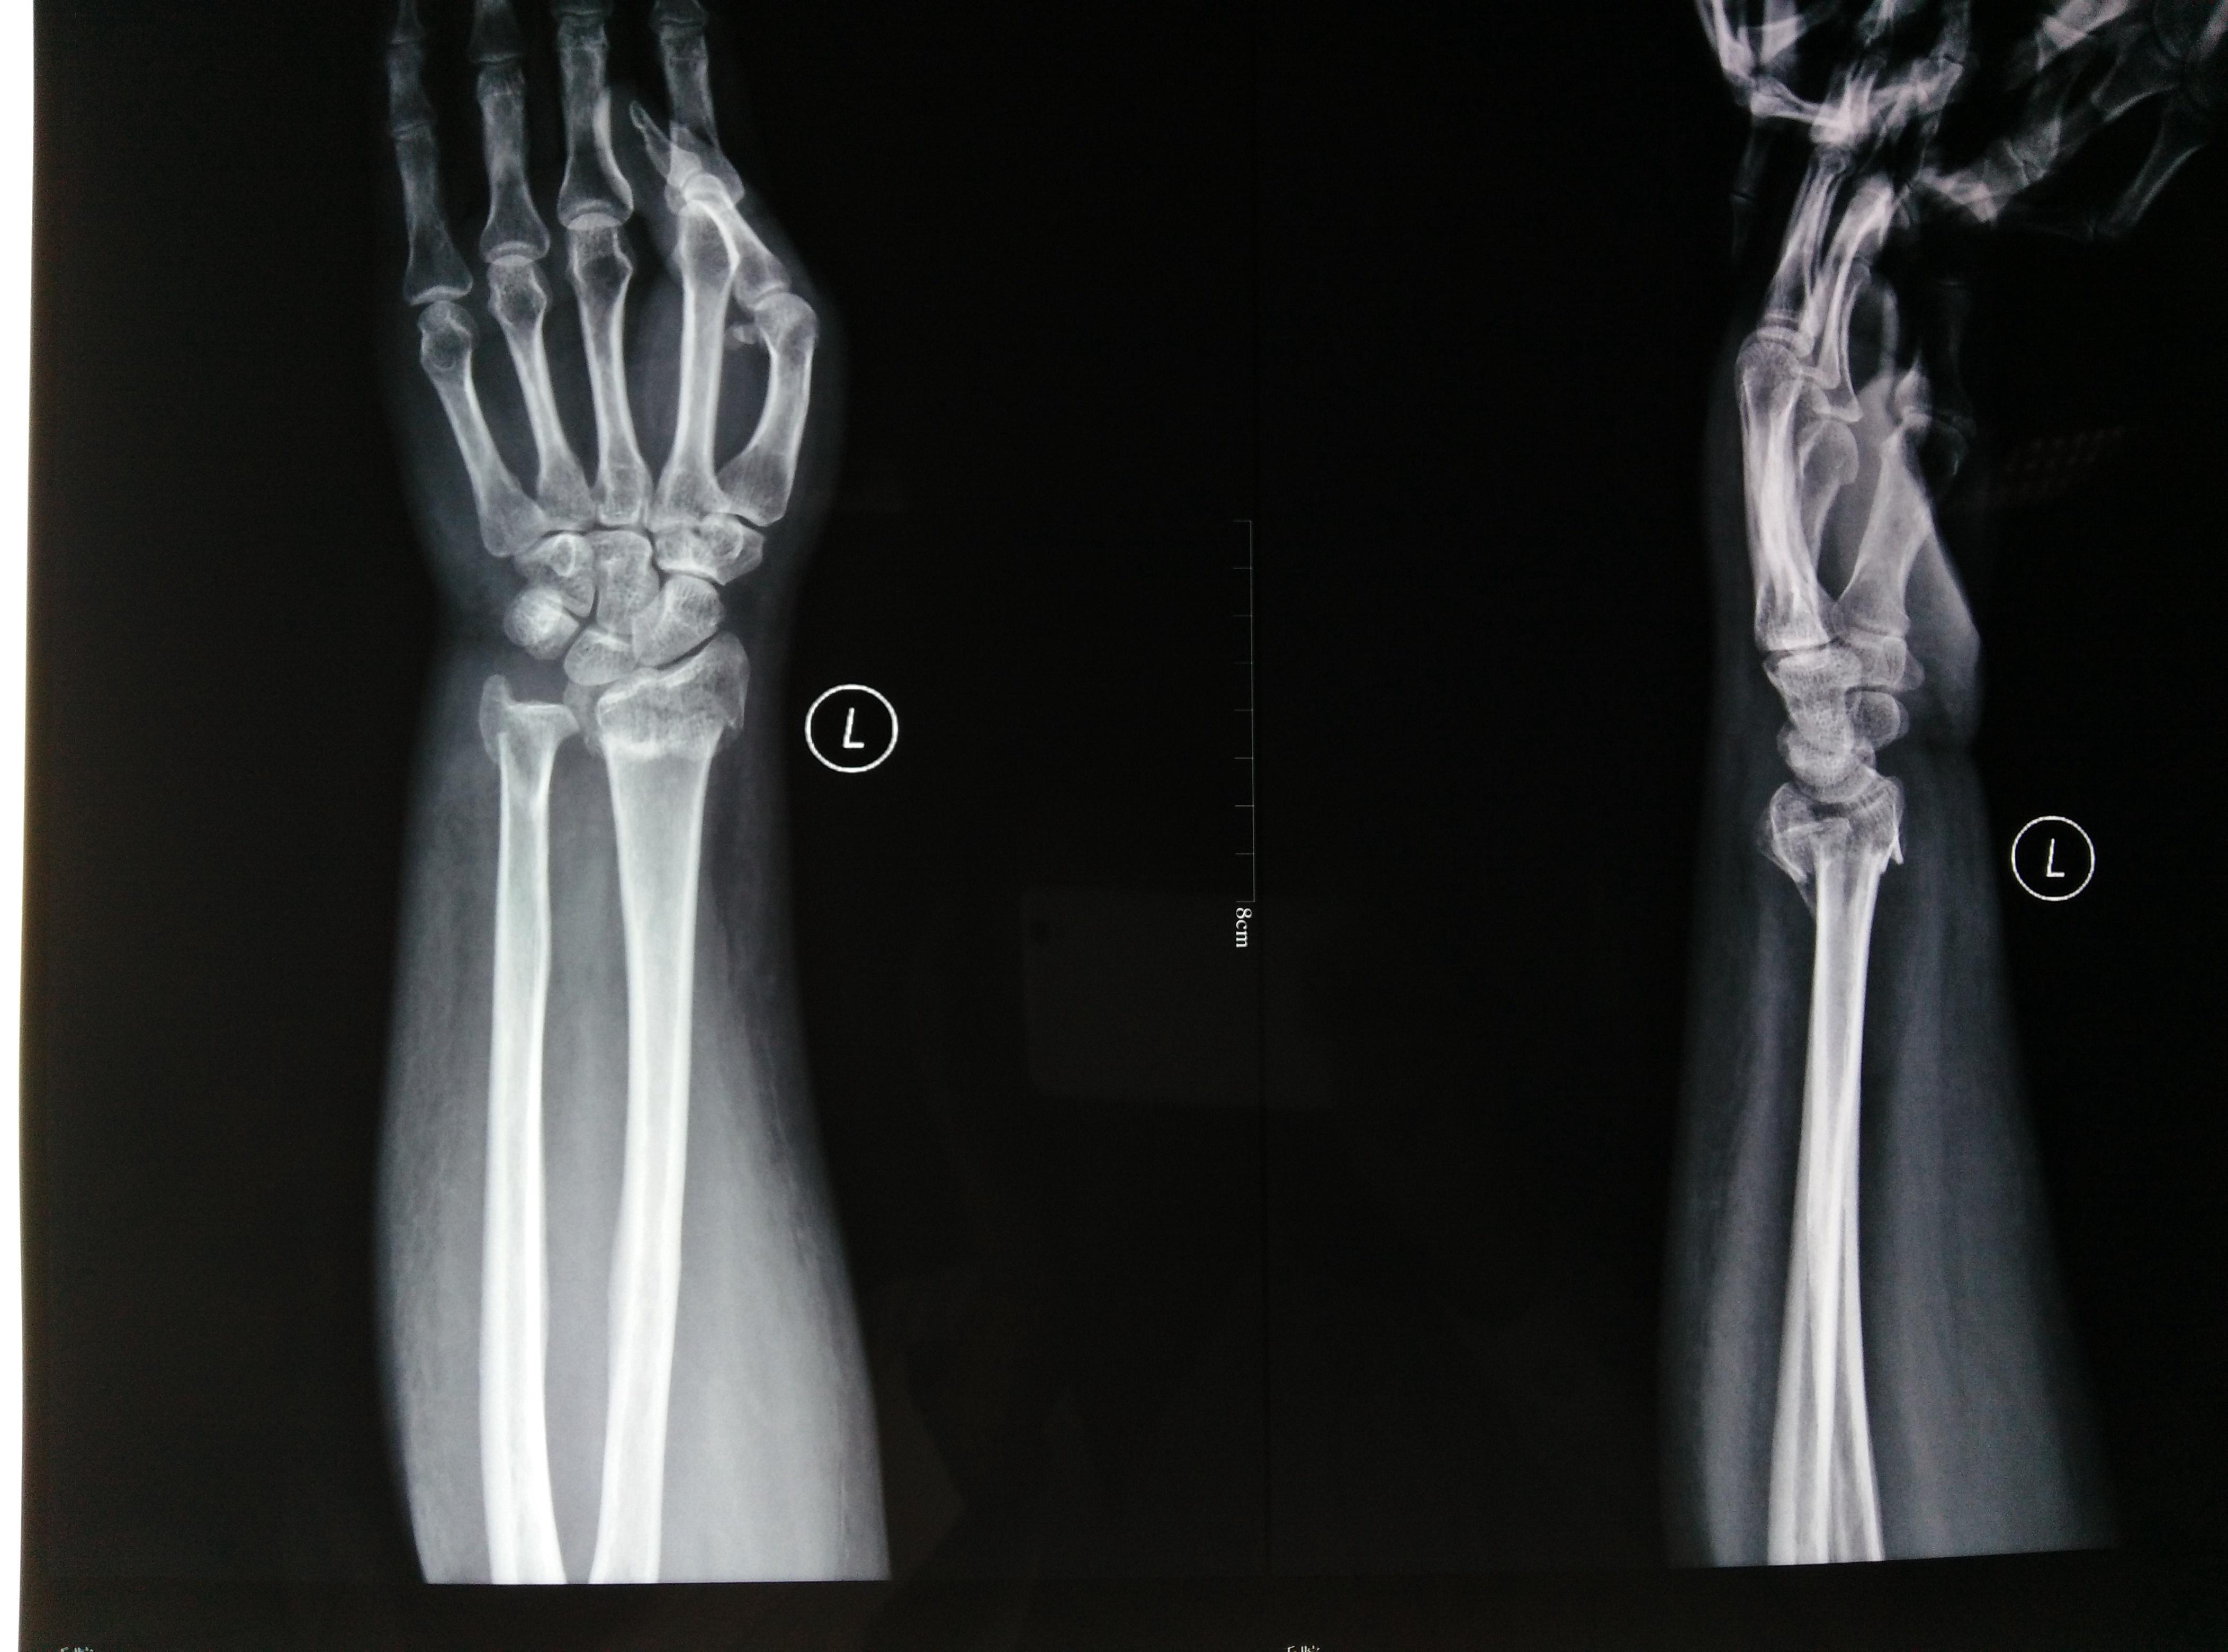

一例,小儿前臂双骨折术前片